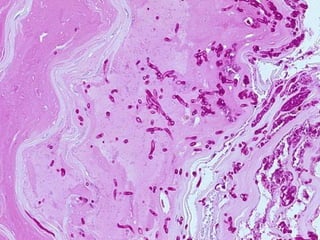

• #107 PAS stain of hyphae, probably scrapings.

• #108 PAS stain of hyphae, probably a histologic slice, NOT scrapings.